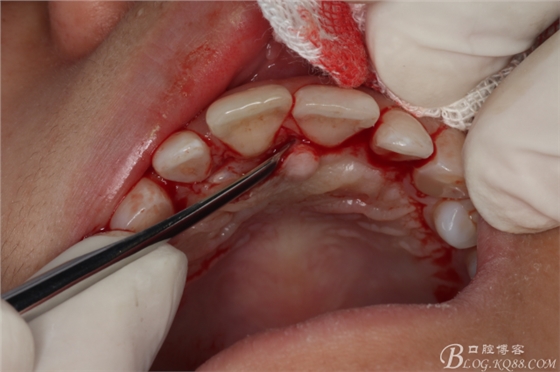

圖7.翻瓣

圖8.翻瓣暴露出鼻腭神經(jīng)管及腭側(cè)骨面